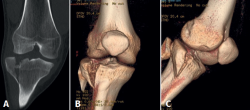

Injured knees always undergo anteroposterior and lateral plain radiographs. A CT scan is also essential for diagnosis, fracture pattern characterization (Figure 1), and surgery planning.

Figure 1. Right knee. Schatzker II close tibial plateau fracture. A: coronal computed tomography (CT) scan; B and C: 3-D tibial plateau fracture reconstruction.